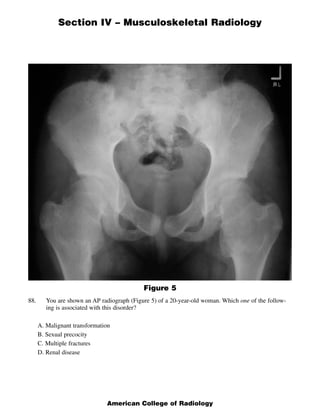

This document contains a radiology case study with 4 images (Figures 1-4) and accompanying questions. Figure 1 shows a lateral cervical spine x-ray. The diagnosis is ankylosing spondylitis based on diffuse bony ankylosis throughout the cervical spine. Figure 2 shows MRI images of the knee with a diagnosis of discoid meniscus due to excessive meniscal tissue. Figure 3 shows x-rays of the leg with a diagnosis of Brodie's abscess, seen as an elongated lytic lesion in the tibia. Figure 4 shows knee images of a 13-year-old boy with a diagnosis of chondroblastoma, seen as a well-defined lesion in the proximal tib